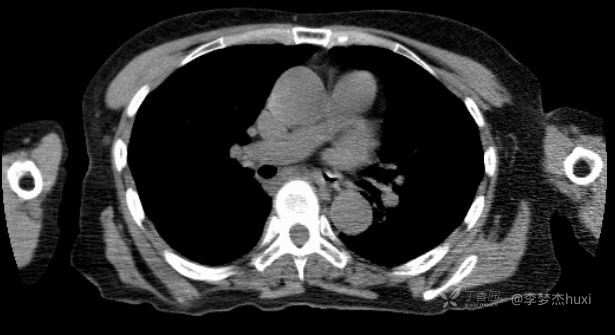

病例女性69岁,仅治疗一次,一个月后肿瘤几乎消失。什么方法这么神奇?

主诉:肺腺癌治疗一次,一月后复查。

讨论:大家猜猜是什么治疗方法?

治疗前:

治疗后: